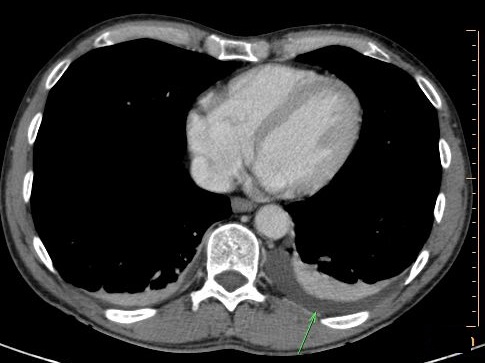

Et une epanchement pleuraux

est le plus frequemment a gauche |